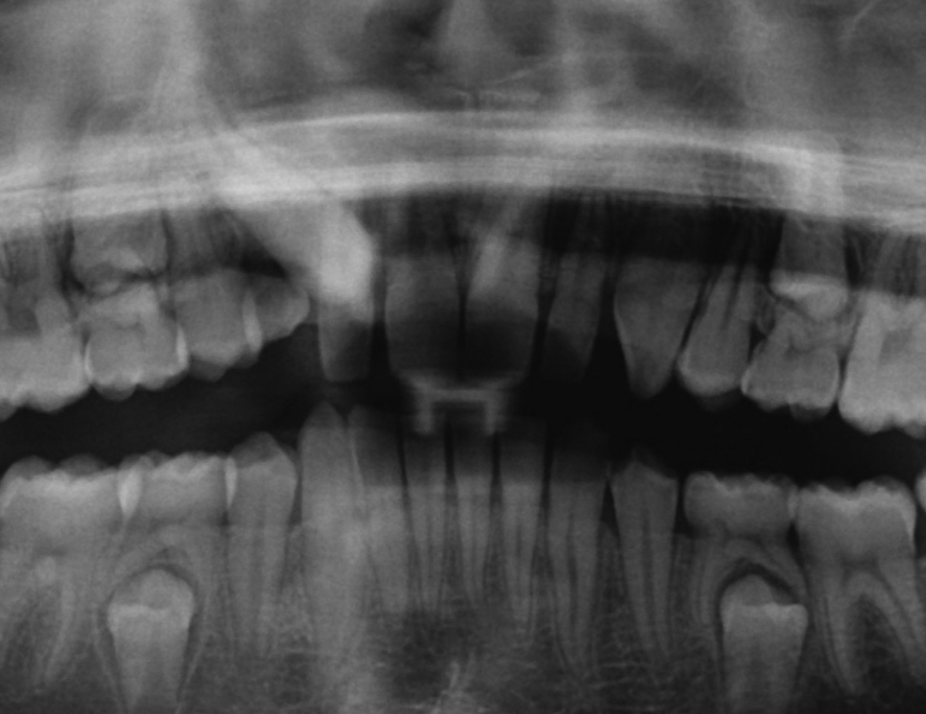

Ectopic Eruption

Ectopically erupting maxillary molar